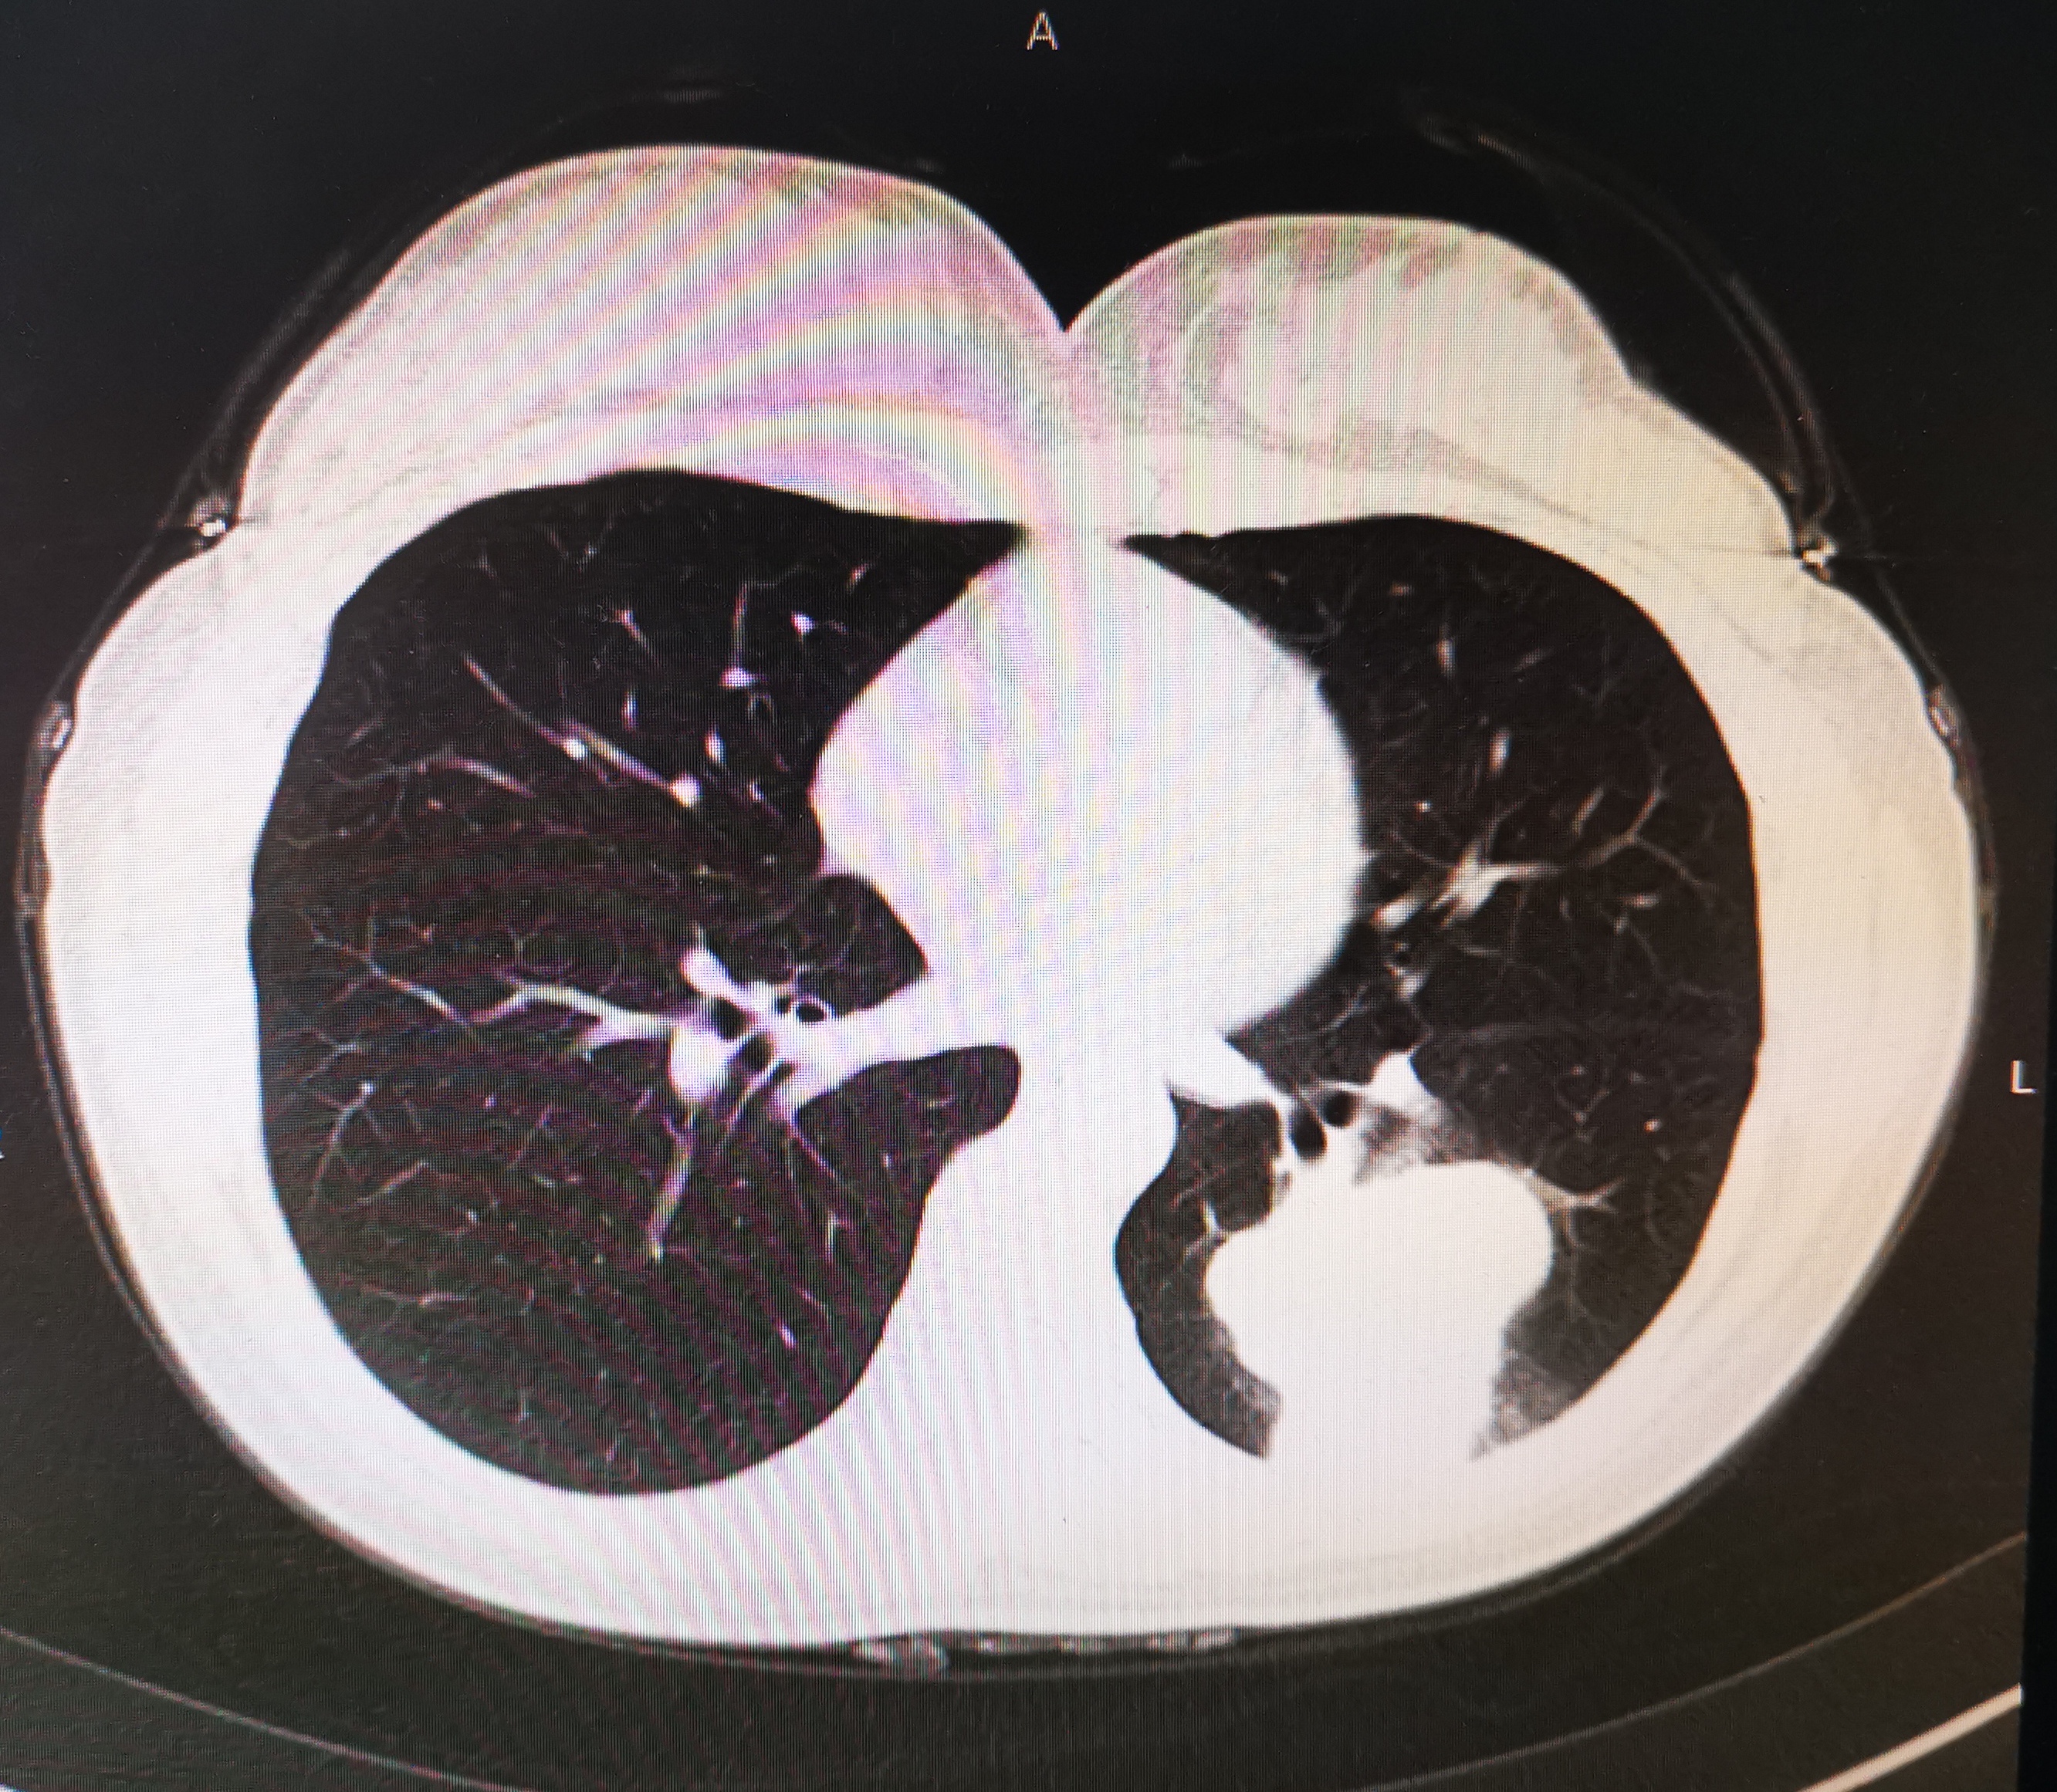

肺癌图片

肺癌图片 脑转移图片